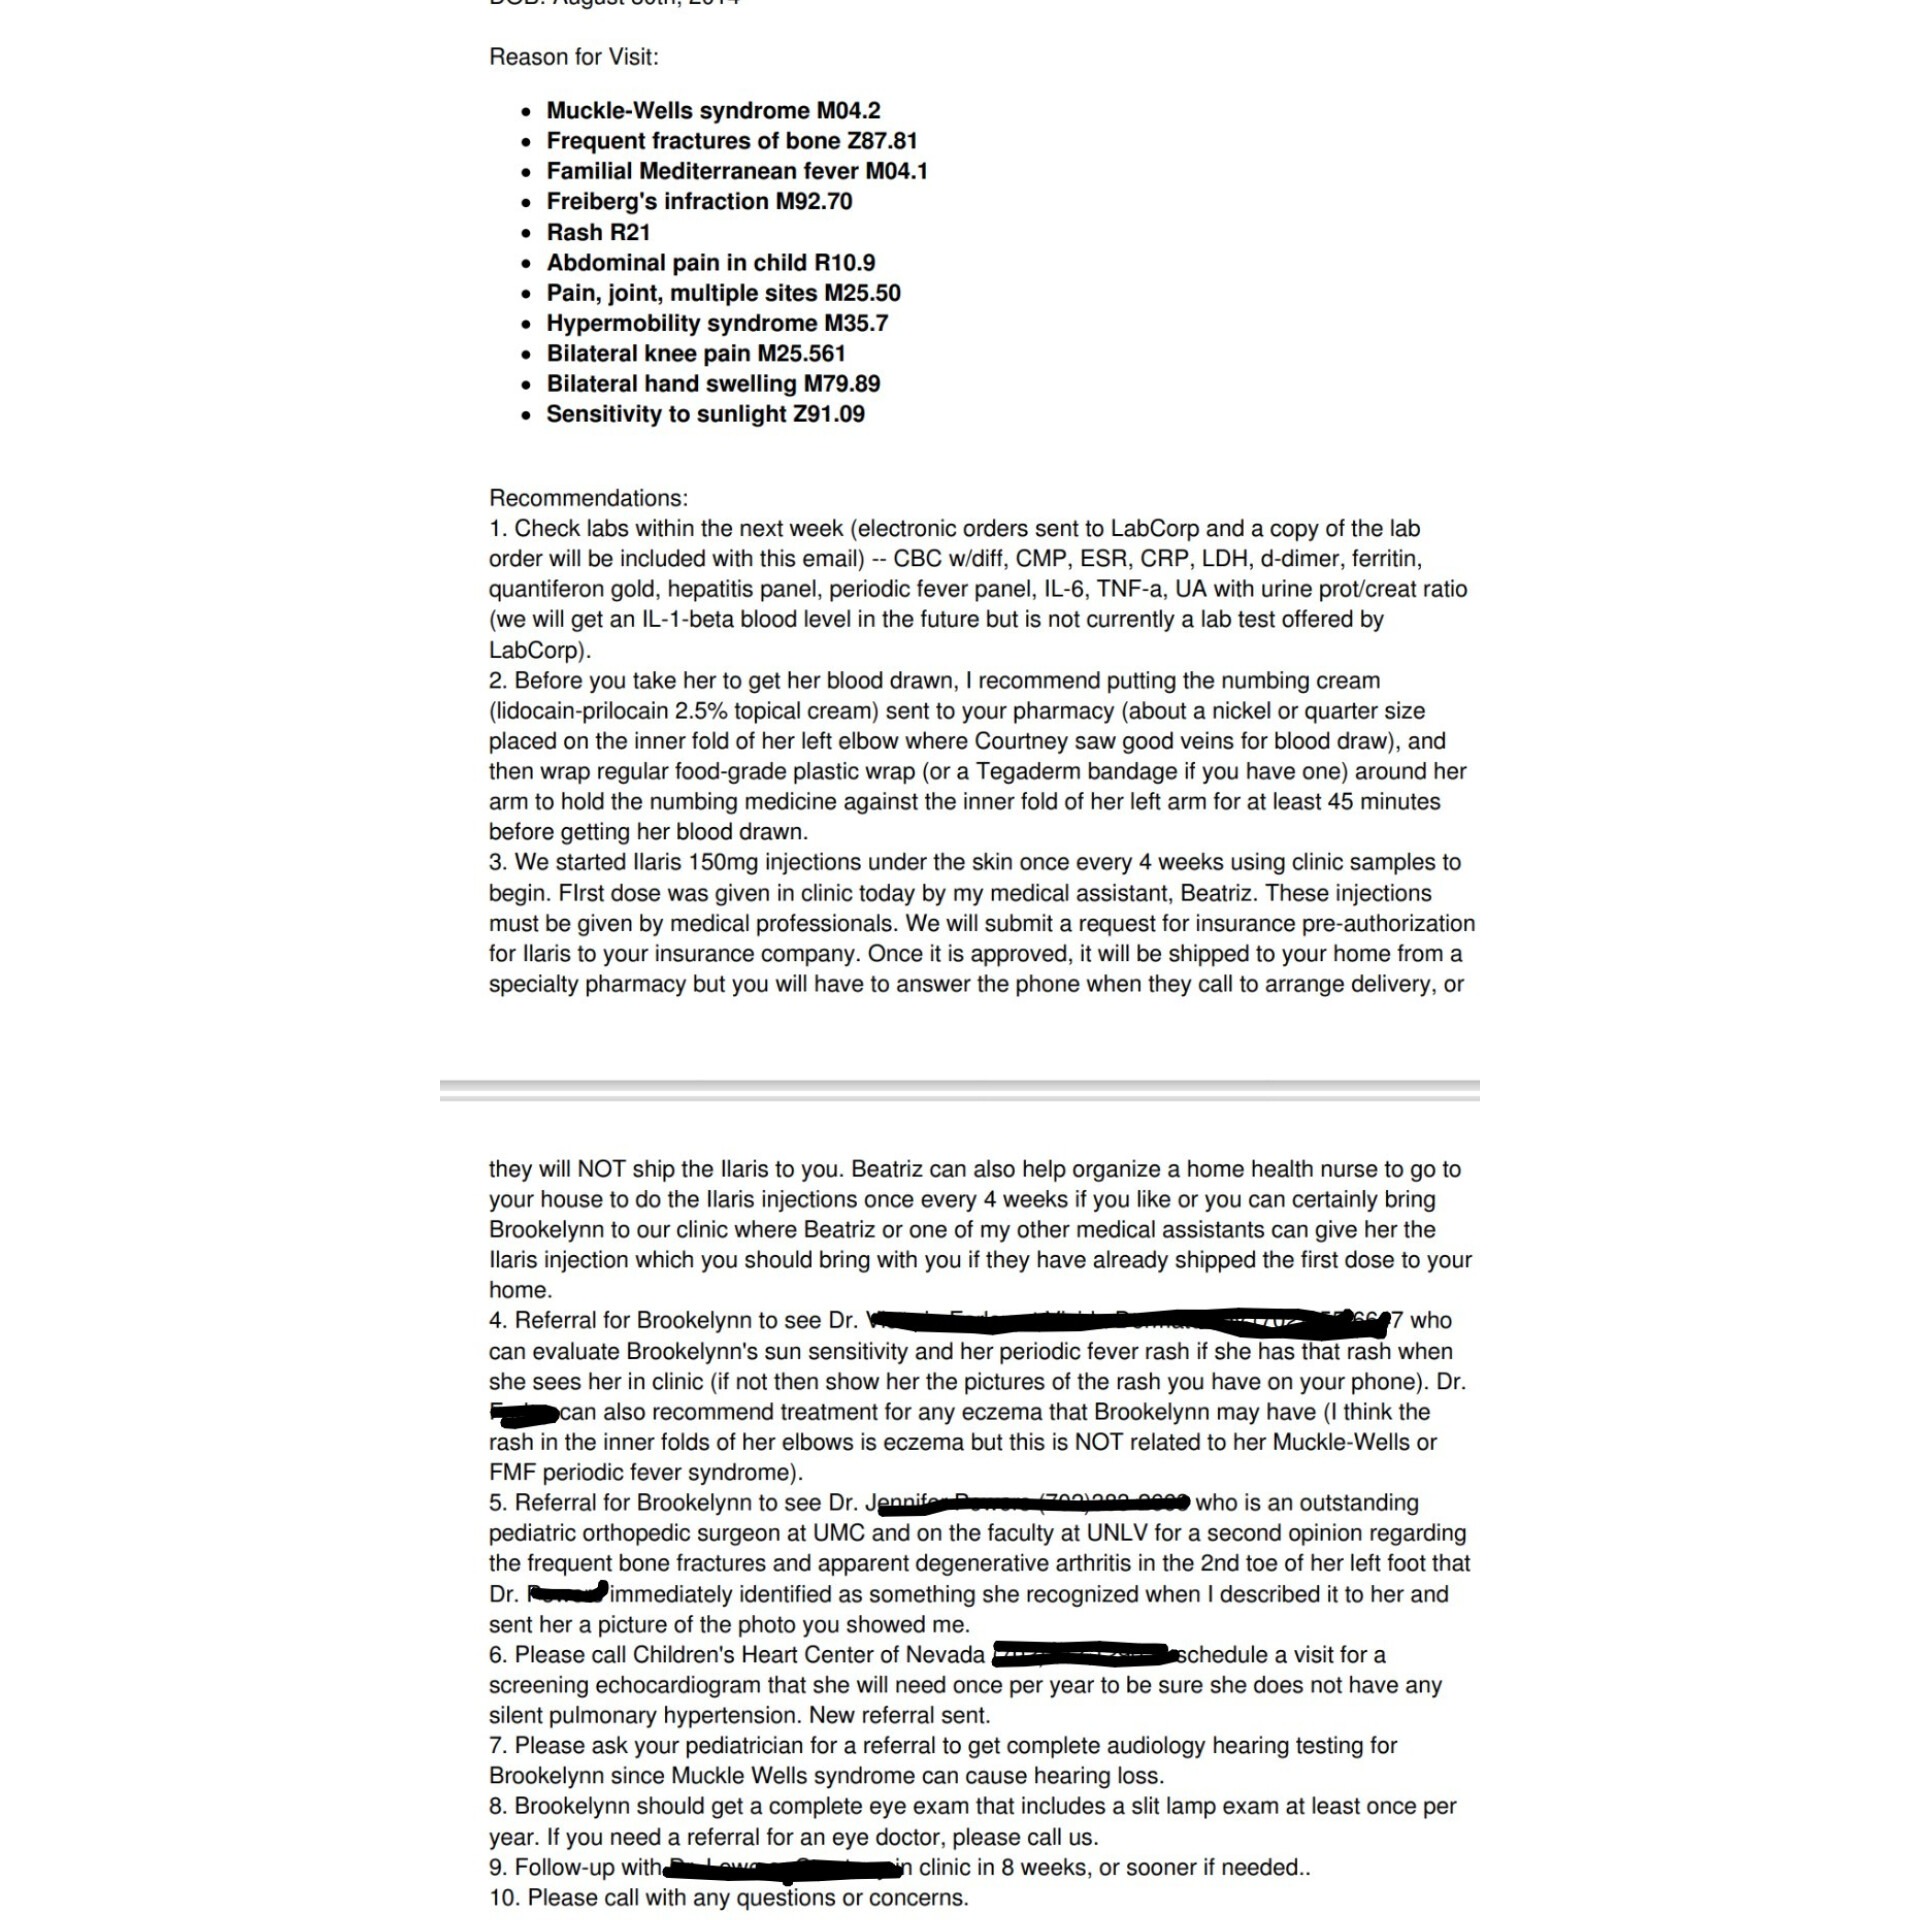

My name is Kortney and I am a single mother of two. The past couple years have been really hard on myself and my kids. With my medical issues, doing it all alone, and other unfortunate life events. But after a VERY VERY long wait to see a REAL Rheumatologist we finally saw him, and our appointment was 4 hours long unpacking the history of Brookelynn, my 11 year old daughter. One positive, was that she didn't have Lupus. But she is now known as "unicorn", a "zebra with polka dots" to this Rheumatologist. My mama heart is broken. As of right now Brookelynn has three rare conditions. One of them is so rare that as of 2024 only 100 cases were diagnosed. This condition is called Muckle Wells Syndrome. The other is a Periodic Fever Syndrome, Familial Mediterranean Fever. We also found out that she has a condition in her foot, Freibergs Infraction. She recently started an injection of antibodies that she will need either weekly, biweekly or monthly. These injections cost $19.000 each. Thankfully as of right now I do not have a cost for those but will once insurance gets involved. With these conditions, Brooke has good and bad days. One day she will be fine, the next she could have her whole body in fight mode for no reason with 106 fever, random stomach pains that will land her in he hospital, back pain so severe she screams in pain, joint pain daily, headaches, skin reactions, playing sports has been her favorite thing and as of right now it's not something she can do because the foot condition can cause pain with walking. Getting to the bottom of her medical issues has taken 11 years as this started when she was a baby. Muckle Wells is not curable, its something she will deal with for the rest of her life and it can cause hearing loss which is devastating. As much as I am thankful to finally have answers, I'm scared.

I am employed with a full time job, as well as 2 part time jobs and work as much as possible to take care of her medications, medical appts, bills, my pets, etc. Although I am working these jobs I'm also missing a lot of work for all of her specialist visits, unpaid. Which has put me in a place of almost losing my job. She does have insurance but the coverage is limited. The constant labs, office visits, tests, medications, etc have me drowning as a single mom.